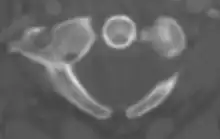

In anatomy, the atlas (C1) is the most superior (first) cervical vertebra of the spine and is located in the neck.

The atlas's chief peculiarity is that it has no body,[3] which has fused with the next vertebra.[4] It is ring-like and consists of an anterior and a posterior arch and two lateral masses.

The lateral masses are the most bulky and solid parts of the atlas, in order to support the weight of the head.

Each carries two articular facets, a superior and an inferior.

- The superior facets are of large size, oval, concave, and approach each other in front, but diverge behind: they are directed upward, medially, and a little backward, each forming a cup for the corresponding condyle of the occipital bone, and are admirably adapted to the nodding movements of the head. Not infrequently they are partially subdivided by indentations which encroach upon their margins.

- The inferior articular facets are circular in form, flattened or slightly convex and directed downward and medially, articulating with the axis, and permitting the rotatory movements of the head.

Vertebral foramen

Just below the medial margin of each superior facet is a small tubercle, for the attachment of the transverse atlantal ligament which stretches across the ring of the atlas and divides the vertebral foramen into two unequal parts:

- the anterior or smaller receiving the odontoid process of the axis

- the posterior transmitting the spinal cord (medulla spinalis) and its membranes

This part of the vertebral canal is of considerable size, much greater than is required for the accommodation of the spinal cord.